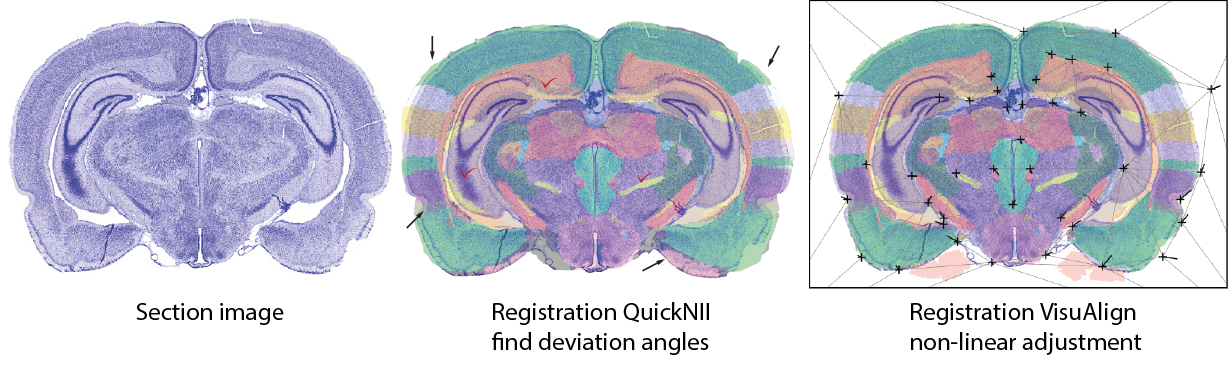

Tools for anatomical landmark based registration of mouse and rat 2D brain images to 3D reference atlases.

Triplet-ilus_registration.png